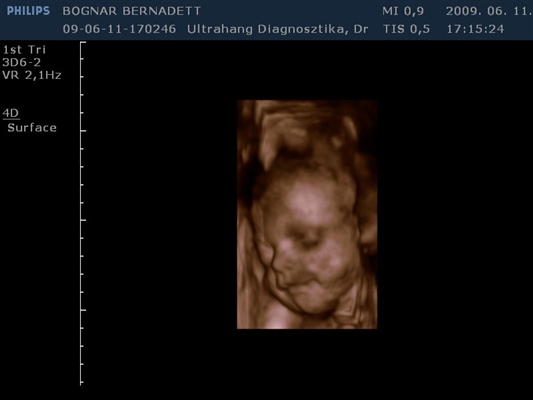

Kb. 3,5 hete én is voltam 4D-n és egy egész jó kis kép kerekedett belőle, majd felteszem.